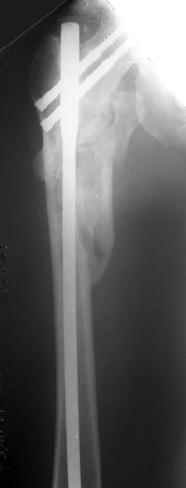

a> Диагноз Закрытый оскольчатый подвертельный перелом правой

a> бедренной кости со смещением отломков,

a> оскольчатый перелом большого вертела, отрывной перелом малого вертела.

Наверно, можно и так сказать, но можно и тоже самое - 4-фрагментный вертельный перелом. Выбор тот же, но с учетом молодого возраста реконструкционный гвоздь тут более применим. Вот уже наш пример.